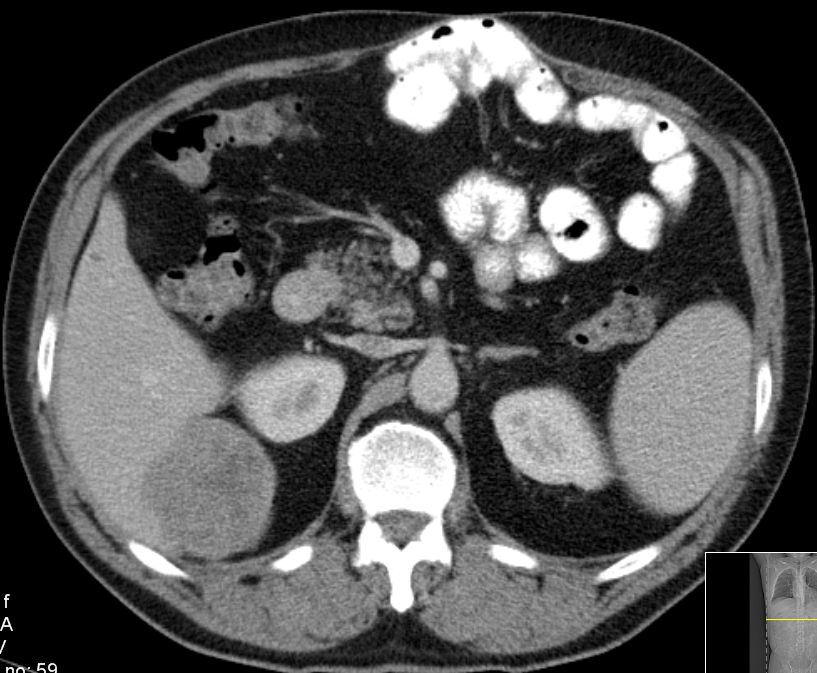

| retroperitoneal | 43-jähriger Mann mit großer Raumforderung im Abdomen.

Undifferenziertes Weichteilsarkom.![]() |